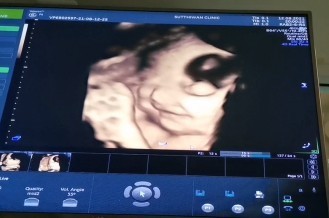

น้องให้ดูหน้าแค่นี้ค่ะ 55